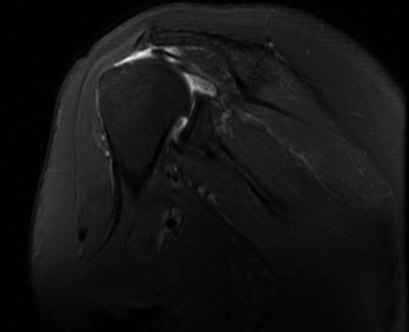

但庄阿姨一听要手术连连拒绝,又回去了。这一拖又是一年,今年3月份,庄阿姨肩关节长期疼痛难忍,甚至已严重影响日常生活,才再次找到薛主任。其术前X线片提示:“右肱骨头向上半脱位,右肩关节退行性病变”;术前MRI提示:“右肩巨大肩袖撕裂,冈上肌脂肪浸润,右肱骨头上移,关节腔积液”。